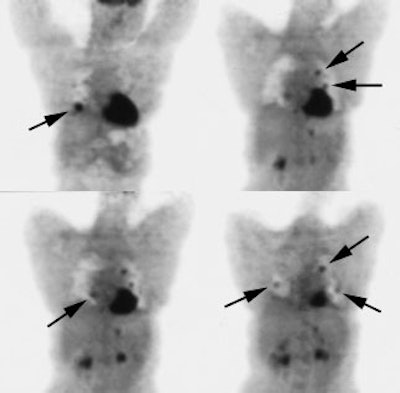

Recurrent Hurthle cell carcinoma: The patient had a history of Hurthle cell carcinoma of the thyroid. Pulmonary metastases are significantly more evident on the coincidence FDG PET examination (below left black arrows) when compared to the I131 scan (below right blue arrows). A CT scan confirmed the presence of pulmonary metastases (below). Note that a subtle bone metastasis to the high left parietal bone can be seen on I131 images. The FDG PET exam did not include this region. |